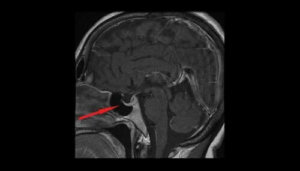

Näkökenttä, CT-skannaus ja aivojen magneettikuvaus ovat kaikista merkittävimpiä kokeita, jotka auttavat diagnoosin vahvistamisessa.